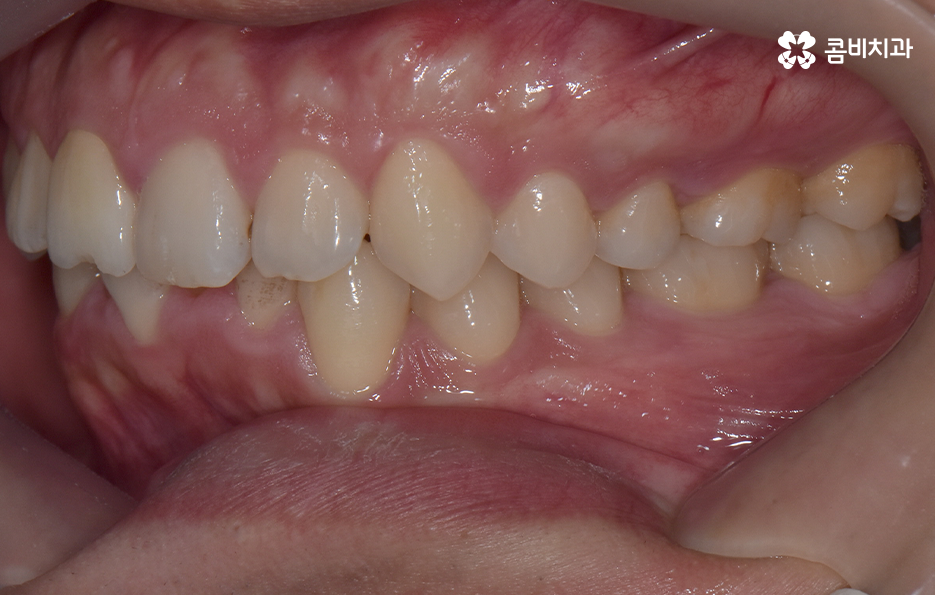

하지만 위에 보시는 환자분의 사례는 윗니와 아랫니의 교합을 고려하고 얼굴형, 골격 등을 고려했을 때도 아랫니만 교정이 가능했던 사례인데 일반적으로 윗니가 아랫니를 살짝 덮고 있어야 하는데 아랫니의 앞니 부분이 유독 안으로 들어와 있었기 때문에 아랫니교정 만으로도 치아교정이 가능했던 사례라고 보시면 좋을 거예요

위 환자분의 사례로 보면 아랫니 중에 하나가 유독 앞으로 튀어나와 있고 나머지 치아는 안으로 들어가 있기 때문에 교합으로 따져볼 때는 아랫니를 전체적으로 앞으로 이동시켜야 했기 때문에 비발치로도 충분히 교정이 가능했고 아랫니교정 만으로도 치료가 가능했어요